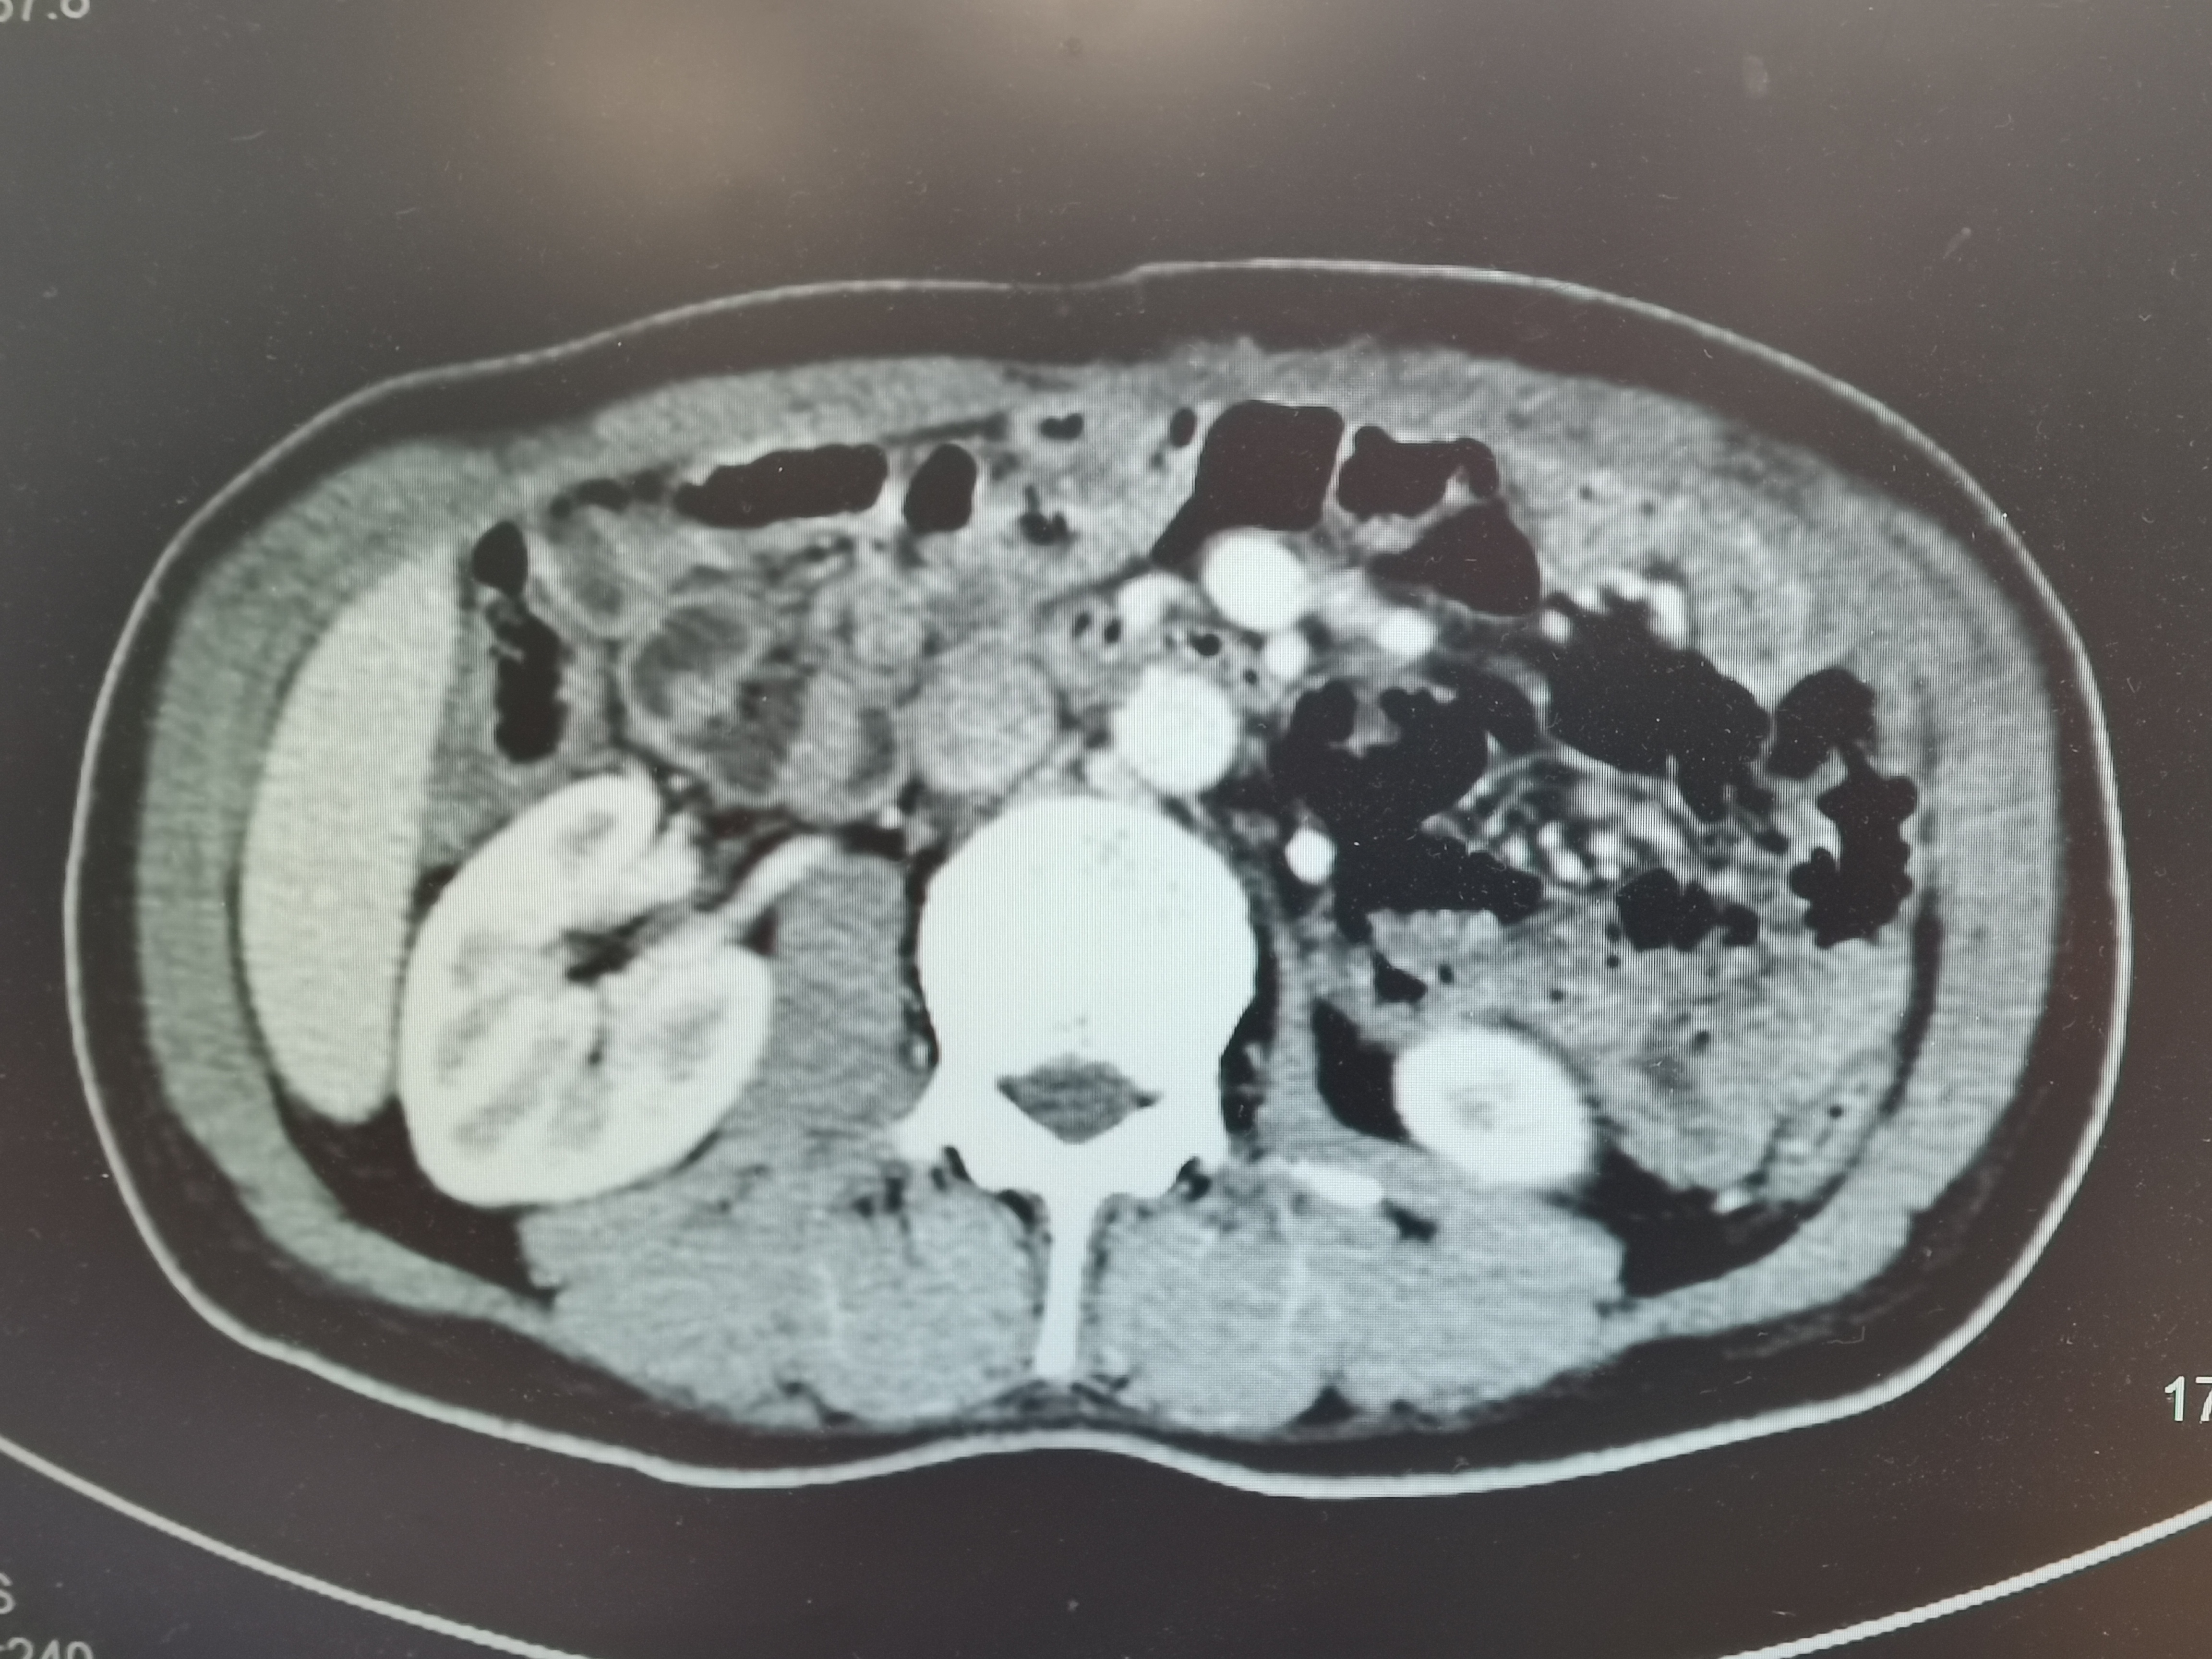

术后腹部CT:病灶已切除